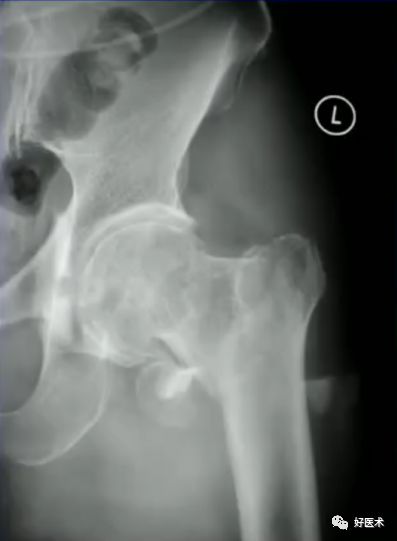

病例一:女 94岁

体表定位与撬棒置顶

撬棒置顶后内收情况

正位进针位置调整情况

主钉插入后的导针正侧位